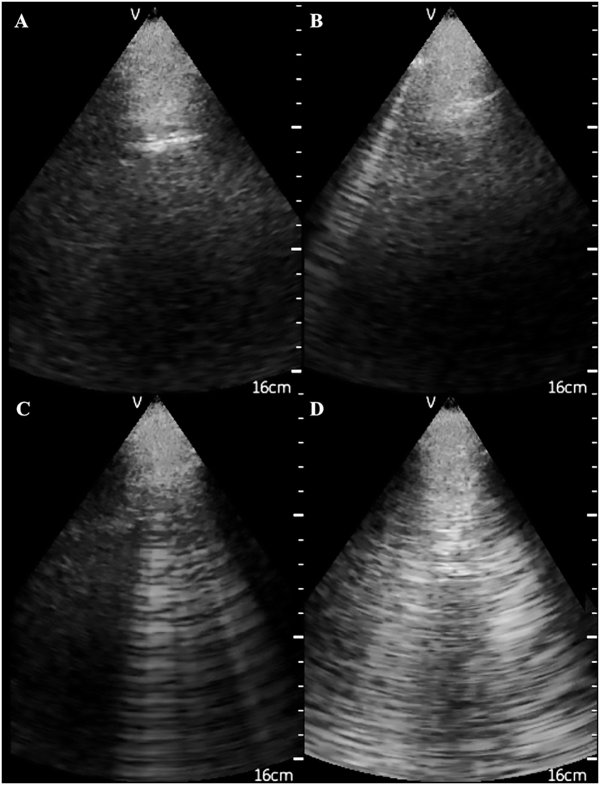

During the last decade, a novel and easy to apply ultrasound (US) technique to quantify water excess in the lungs in these patients has been developed []. Lung US takes advantage of basic principles of ultrasonography, i.e. excessive lung water in the thickened subpleural interlobular septa completely reflect the US beam, forming highly echogenic structures, the US-B lines [], which are hyperechoic reverberation artefacts between the subpleural interlobular septa and the overlying pleura (Figure 2) []. In a cross-sectional analysis of baseline data from the Lung water by UltraSound guided Treatment to prevent death and cardiovascular complications in high risk end-stage renal disease patients with cardiomyopathy (LUST) study, lung US was superior to clinical criteria in detecting and monitoring volume excess in haemodialysis patients []. The feasibility and the validation of this technique in HD patients were examined in a study including 75 HD patients []. In this study, the number of US-B lines was reproducible and had small interoperator variability. Of note, lung water as estimated by this technique modestly correlated with LV mass (r = 0.28, P = 0.01), diastolic dysfunction and LV filling pressures [early transmitral diastolic velocity (E): r = 0.31, P = 0.008; early transmitral diastolic velocities ratio (E:e‵): r = 0.48, P < 0.001], but was only weakly associated with the hydration status as measured by bioimpedance analysis []. Previous ultrasonographic techniques include measurement of the IVC diameter and collapsibility []. Measurement of IVC diameter, relative plasma volume and bioimpedance analysis during a dry weight reduction protocol guided by clinical criteria has been examined in a pilot study in 16 incident HD patients []. In this study, all methods, except bioimpedance, were overtly inadequate for capturing meaningful volume changes induced by a dry weight reduction intervention []. Recently an automated method to evaluate IVC diameter has been developed, but this device has not yet been tested in dialysis patients []. Although the inferior vena cava reflects central venous pressure, it is a poor marker of hydration status because it may be affected by respiration, right heart function and by intrathoracic or abdominal pressure changes [].

Ultrasonographic appearance of (A) normal lungs and the presence of (B) 1, (C) 4 and (D) 10 US B-lines.